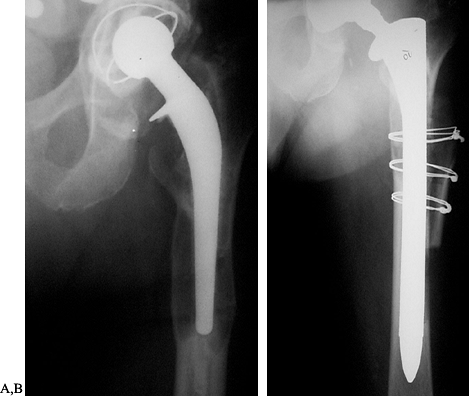

Figure 106.1. A: Periprosthetic fracture treated with plates and strut grafts. B: Refractures with weight bearing. C: Revised with a fully coated component acting as intramedullary fixation reinforced with strut grafts.

![]() |

|